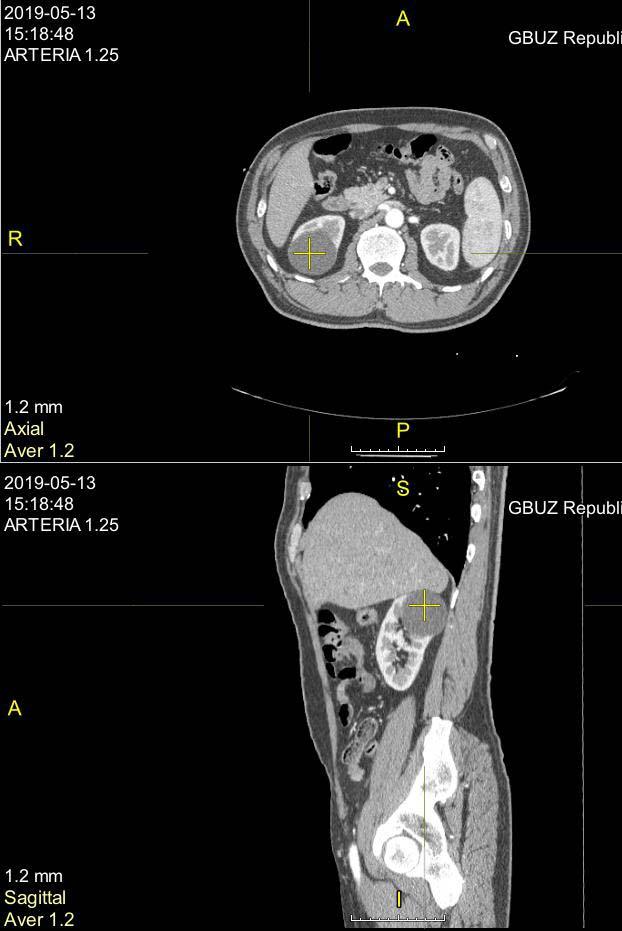

Киста почки.

Киста почки 55 мм (одиночная), медленно растет,

что лучше, с точки зрения надежности и влияния на функцию почки: пункция со склерзированием или лапароскопия.

Здравствуйте! Судя по расположению, безопаснее совершенно точно - пункционная аспирация под УЗ-контролем со склерозированием( под местной анестезией). На функцию почки, при отсутствии осложнений, не повлияет ни один из методов. Удачи!